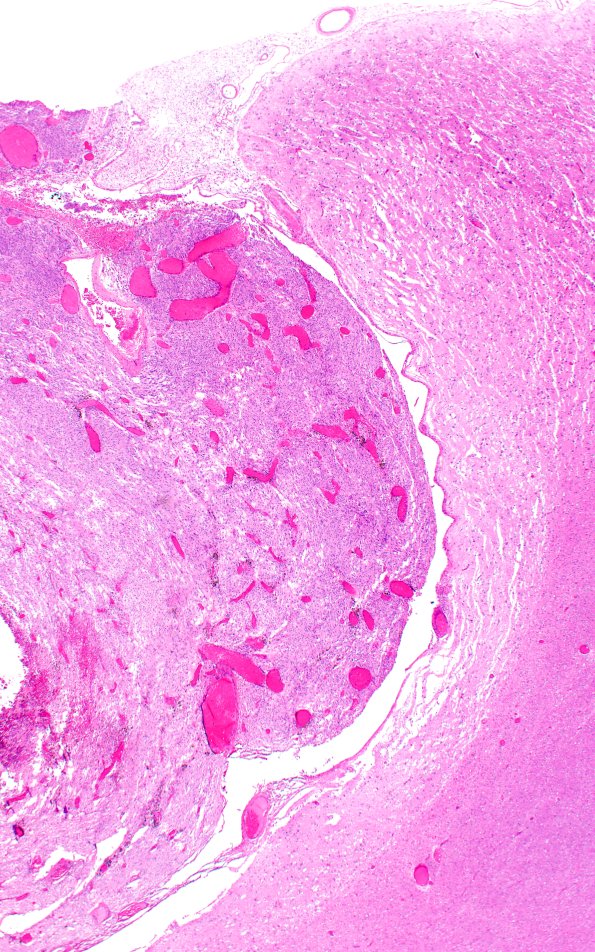

Washington University Experience | NEOPLASMS (MENINGIOMA) | Gross Pathology | 72E2 NCL (Case 72) H&E 2X

72E2,3 The right margin with the brain in image #72E1 is shown at several magnifications. There are a few remaining neurons containing ceroid/lipofuscin in the cortex. (H&E)